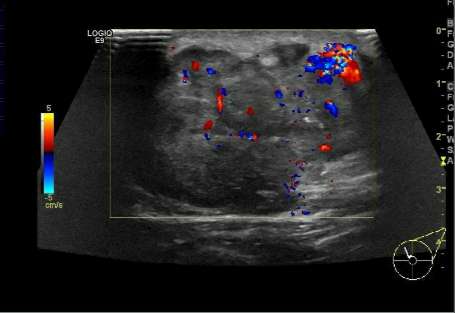

7.乳腺结节的血供。

良性病变多是无血供的实性结节,而恶性结节由于对营养成分的过量摄取,往往其周围的血管数目、血供丰富,往最高血流速度大于20cm/s,血流阻力指数RI≥0.7,这是恶性结节的特征性表现。

结节内血供丰富,是恶性的征象。